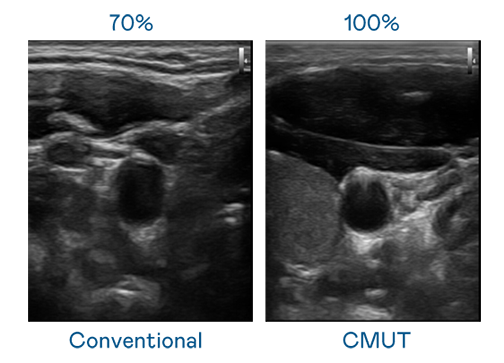

CMUT 技术是一种用电容式微机电元件来产生超音波讯号的技术。与传统 PZT 压电式技术相比,CMUT 频宽增加 30%,更宽频的超音波讯号让影像解析度大幅提升,是实现高影像品质医疗超音波扫描、促进精准医疗发展的关键技术。

大频宽带来超清晰影像

超音波影像的解析度高低,首先取决于探头能发出的讯号频宽。博天堂918 CMUT 可提供高清晰的超音波讯号,提供高频宽、高灵敏度、影像纹理细节更高的超音波影像,协助医护人员缩短影像判读时间及利用精准的医疗影像进行诊断。